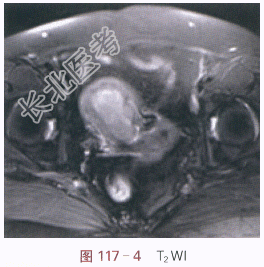

(1)症状:女,59岁,不规则阴道流血2月余。

(2)体格检查:诊断性刮宫未见异常。

影像学资料如图117-1~图117-5所示。

读片分析:子宫稍增大,内膜弥漫性增厚,结合带中断。增强扫描后,增厚的内膜呈不规则强化,局部浸润超过肌层1/2厚度。